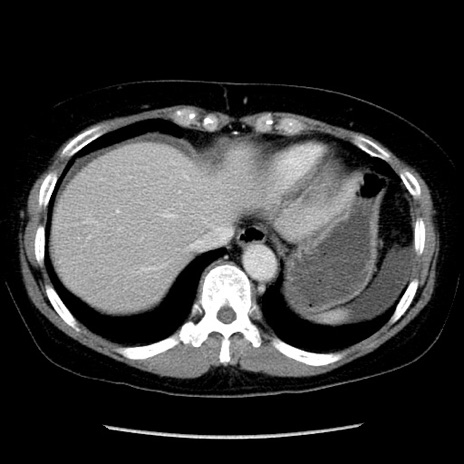

冠状断像

症例6(横断像)

【症例】50歳代女性

【主訴】下腹部痛

【既往歴】卵巣癌術後(8年前に当院で卵巣摘出)

【身体所見】 意識清明、腹部:平坦、腸蠕動音→、やや硬、下腹部自発痛・圧痛あり、反跳痛あり、筋性防御なし。

【データ】WBC 16000、CRP 0.01